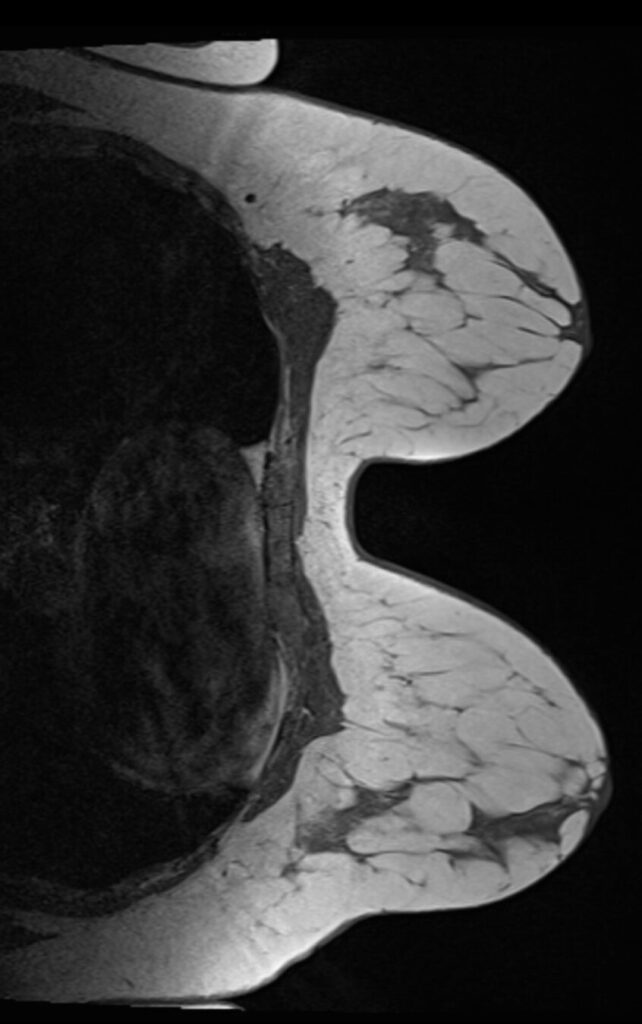

Die Magnetresonanztomographie der Brust, auch MRT Brust oder Mamma MRT genannt, ist ein strahlen- und schmerzfreies Bildgebungsverfahren. Dieses ermöglicht die detaillierte Darstellung der Brust, genauer die Struktur und Beschaffenheit des Brustgewebes. Eine regelmäßige Untersuchung der Brust zur Früherkennung kann dabei helfen, Veränderungen in der Brust zu entdecken und die Erfolgsaussichten einer individuellen Therapie zu verbessern.

Die Magnetresonanztomographie (MRT) der Brust ist ein bildgebendes Verfahren, das starke Magnetfelder und Radiowellen nutzt, um detaillierte Bilder des Brustgewebes zu erstellen. Anders als die Mammographie, bei der Röntgenstrahlen verwendet werden, ist die Mamma MRT strahlenfrei und besonders geeignet, um dichtes Brustgewebe oder Tumore sichtbar zu machen. Die MRT der Brust ermöglicht es 90 von 100 bösartigen Tumoren korrekt nachzuweisen. (Quelle Link)

Die Mamma MRT kommt häufig zum Einsatz, wenn andere bildgebende Verfahren (wie Mammografie oder Ultraschall) nicht ausreichen oder wenn es ein hohes familiäres Risiko für Brustkrebs gibt.